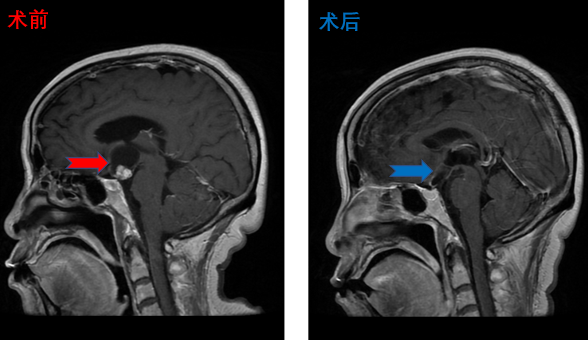

脑干海绵状血管瘤患者影像,术后肢体活动良好、面瘫情况同术前,无新增阳性体征